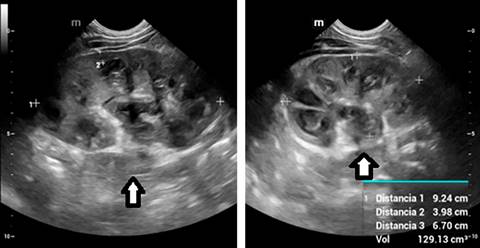

En los paraclínicos de ingreso presentaba anemia moderada, trombocitosis, leucocitosis a expensas de neutrófilos, pruebas de función renal y hepática normales, proteína C reactiva elevada y uroanálisis sugestivo de proceso infeccioso (Tabla 1). En la ecografía de vías urinarias se evidenció aumento del tamaño del riñón izquierdo con dilatación de la pelvis renal y de los cálices centrales y periféricos con material ecogénico en su interior (Figura 1). Por sospecha de absceso renal se inicia antibiótico de amplio espectro (ceftriaxona). El urocultivo de ingreso no mostró crecimiento bacteriano a las 48 horas de incubación. Por el hallazgo por ultrasonido se realiza tomografía donde se identifica dilatación de la pelvis renal izquierda de 25 mm de diámetro por presencia de cálculo obstructivo a nivel de la unión pieloureteral. Completa 14 días de tratamiento antibiótico con resolución de la fiebre y el urocultivo al finalizar la terapia sin crecimiento bacteriano. Por los antecedentes se decide mantener profilaxis antibiótica con cefalosporina de primera generación.

Figura 1: Ecografía renal y de vías urinarias del riñón izquierdo, donde se observa aumento de tamaño. Hay una dilatación notable de la pelvis renal (25 mm) y de los cálices centrales y periféricos, con la presencia de material ecogénico en su interior (flecha blanca).